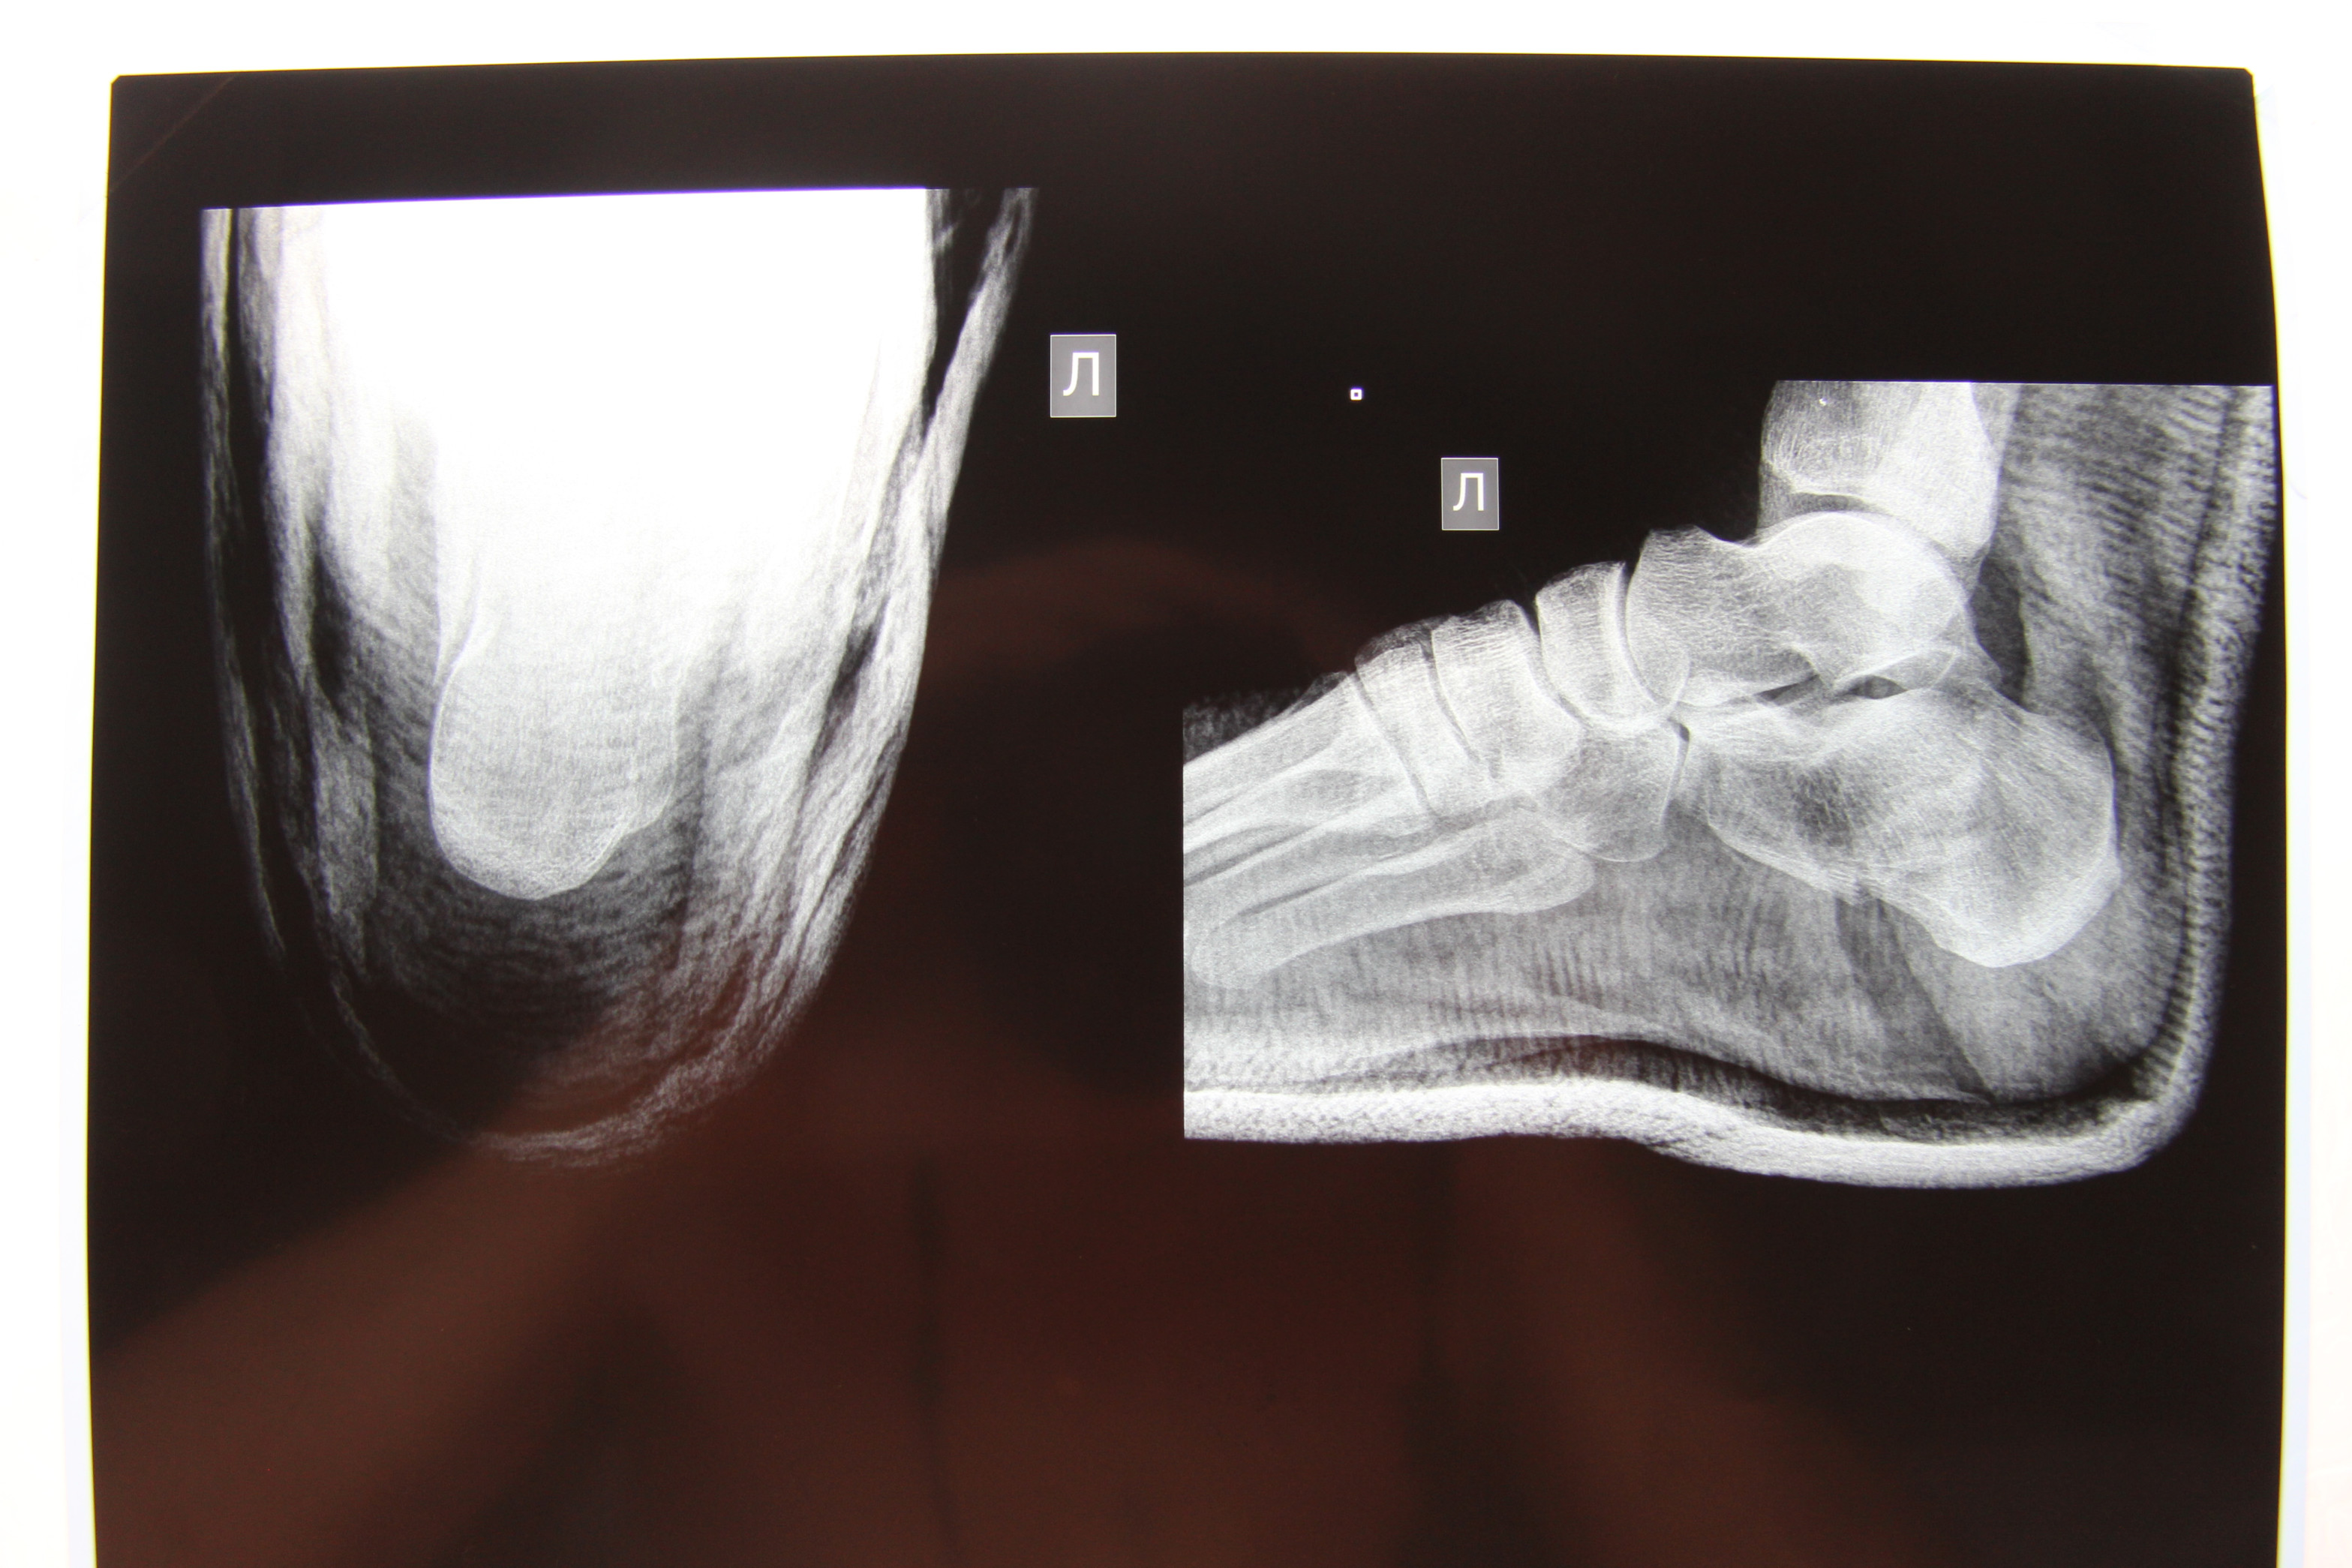

Здравствуйте! Уважаемые доктора, посмотрите пожалуйста снимок перелома пяточной кости, что можете сказать. Серьезный ли там перелом?Мнения у врачей расходятся, кто говорит нужна операция, кто говорит сама срастется. Ни операции, не гипс не наложили, очень переживаем. Спасибо!

Здравствуйте. На представленных рентгенограммах-достаточно тяжелый перелом пяточной кости. К счастью суставная поверхность пяточной кости, участвующая в формировании подтаранного сустава интактна, по крайней мере рентгенологически. Если перелом консолидируется в таком положении, то вероятнее всего будет ограничение подошвенного сгибания и болевой синдром при ходьбе. Чем меньше времени прошло после травмы, тем больше вероятность выполнить данное вмешательство малоинвазивно.